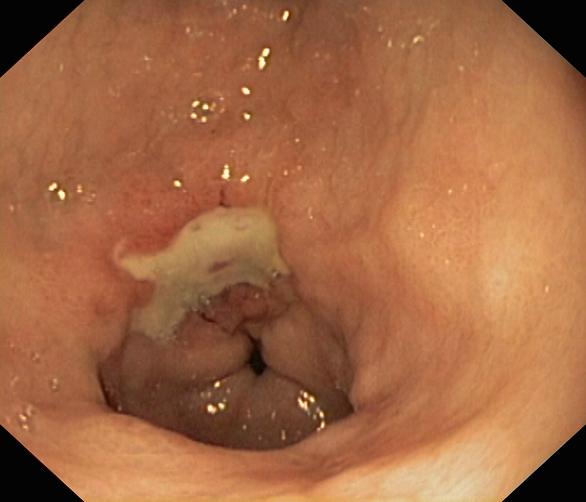

Wrzód trawienny